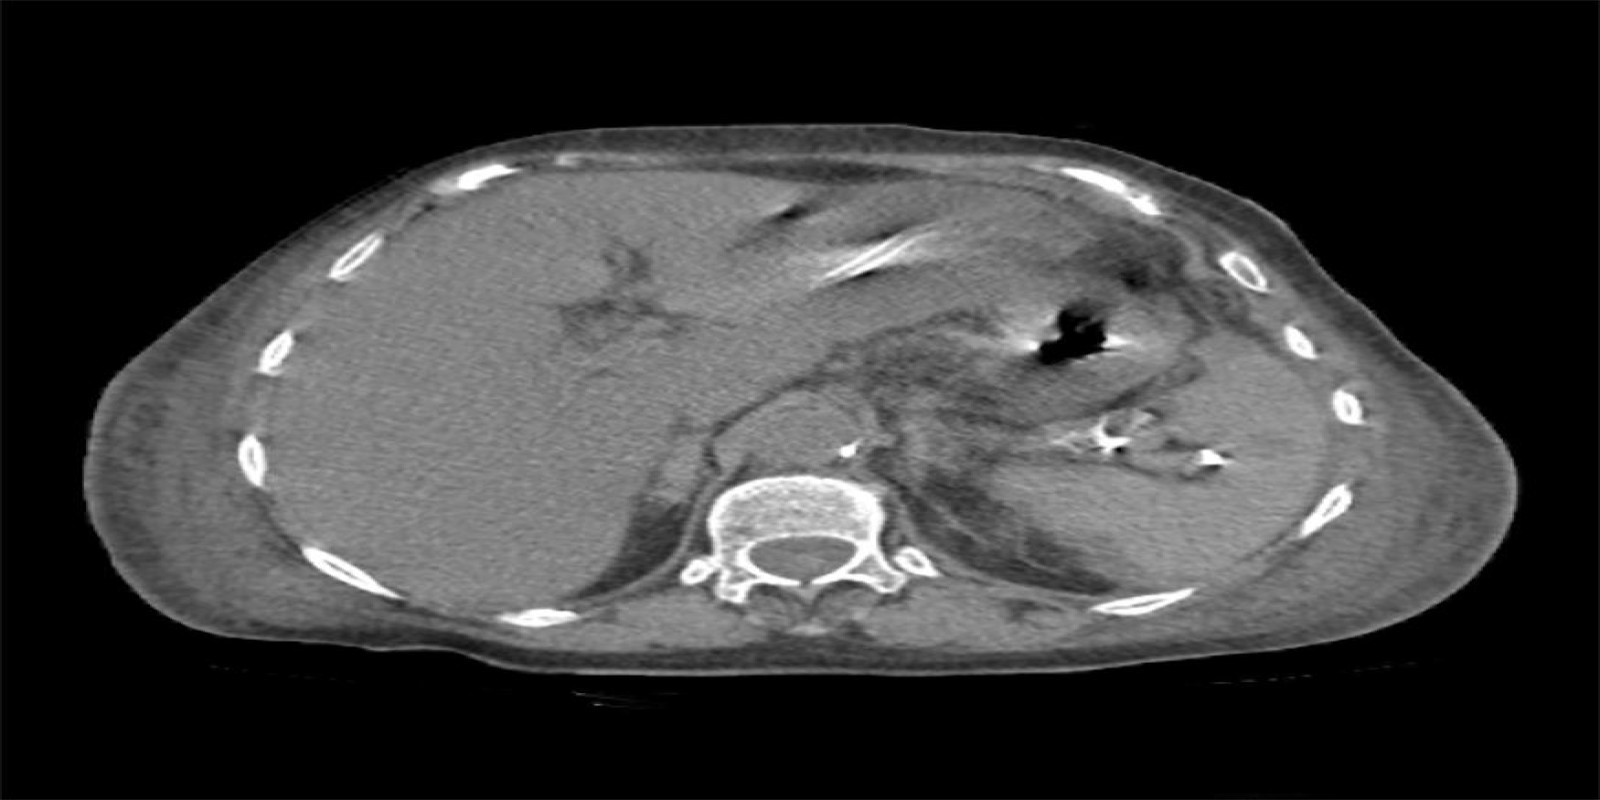

Caso Código 124A de Abscesso Hepático

Cod.: 124A